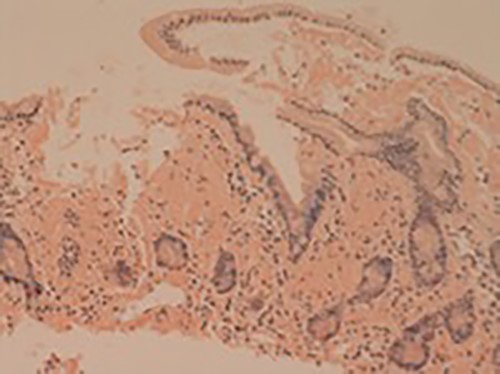

Small bowel mucosa (Congo red, x20): the substance is positive with Congo red stain in keeping with amyloid (salmon pink staining under standard light microscopy).

Her liver biochemistry continued to deteriorate so a transjugular liver biopsy was performed. Histology from both liver and duodenal biopsies was consistent with amyloidosis on Congo red staining (Figs 1 and 2, respectively). A subsequent bone marrow biopsy, organized by the haematologists, revealed a low level infiltrate of plasma cells consistent with multiple myeloma.